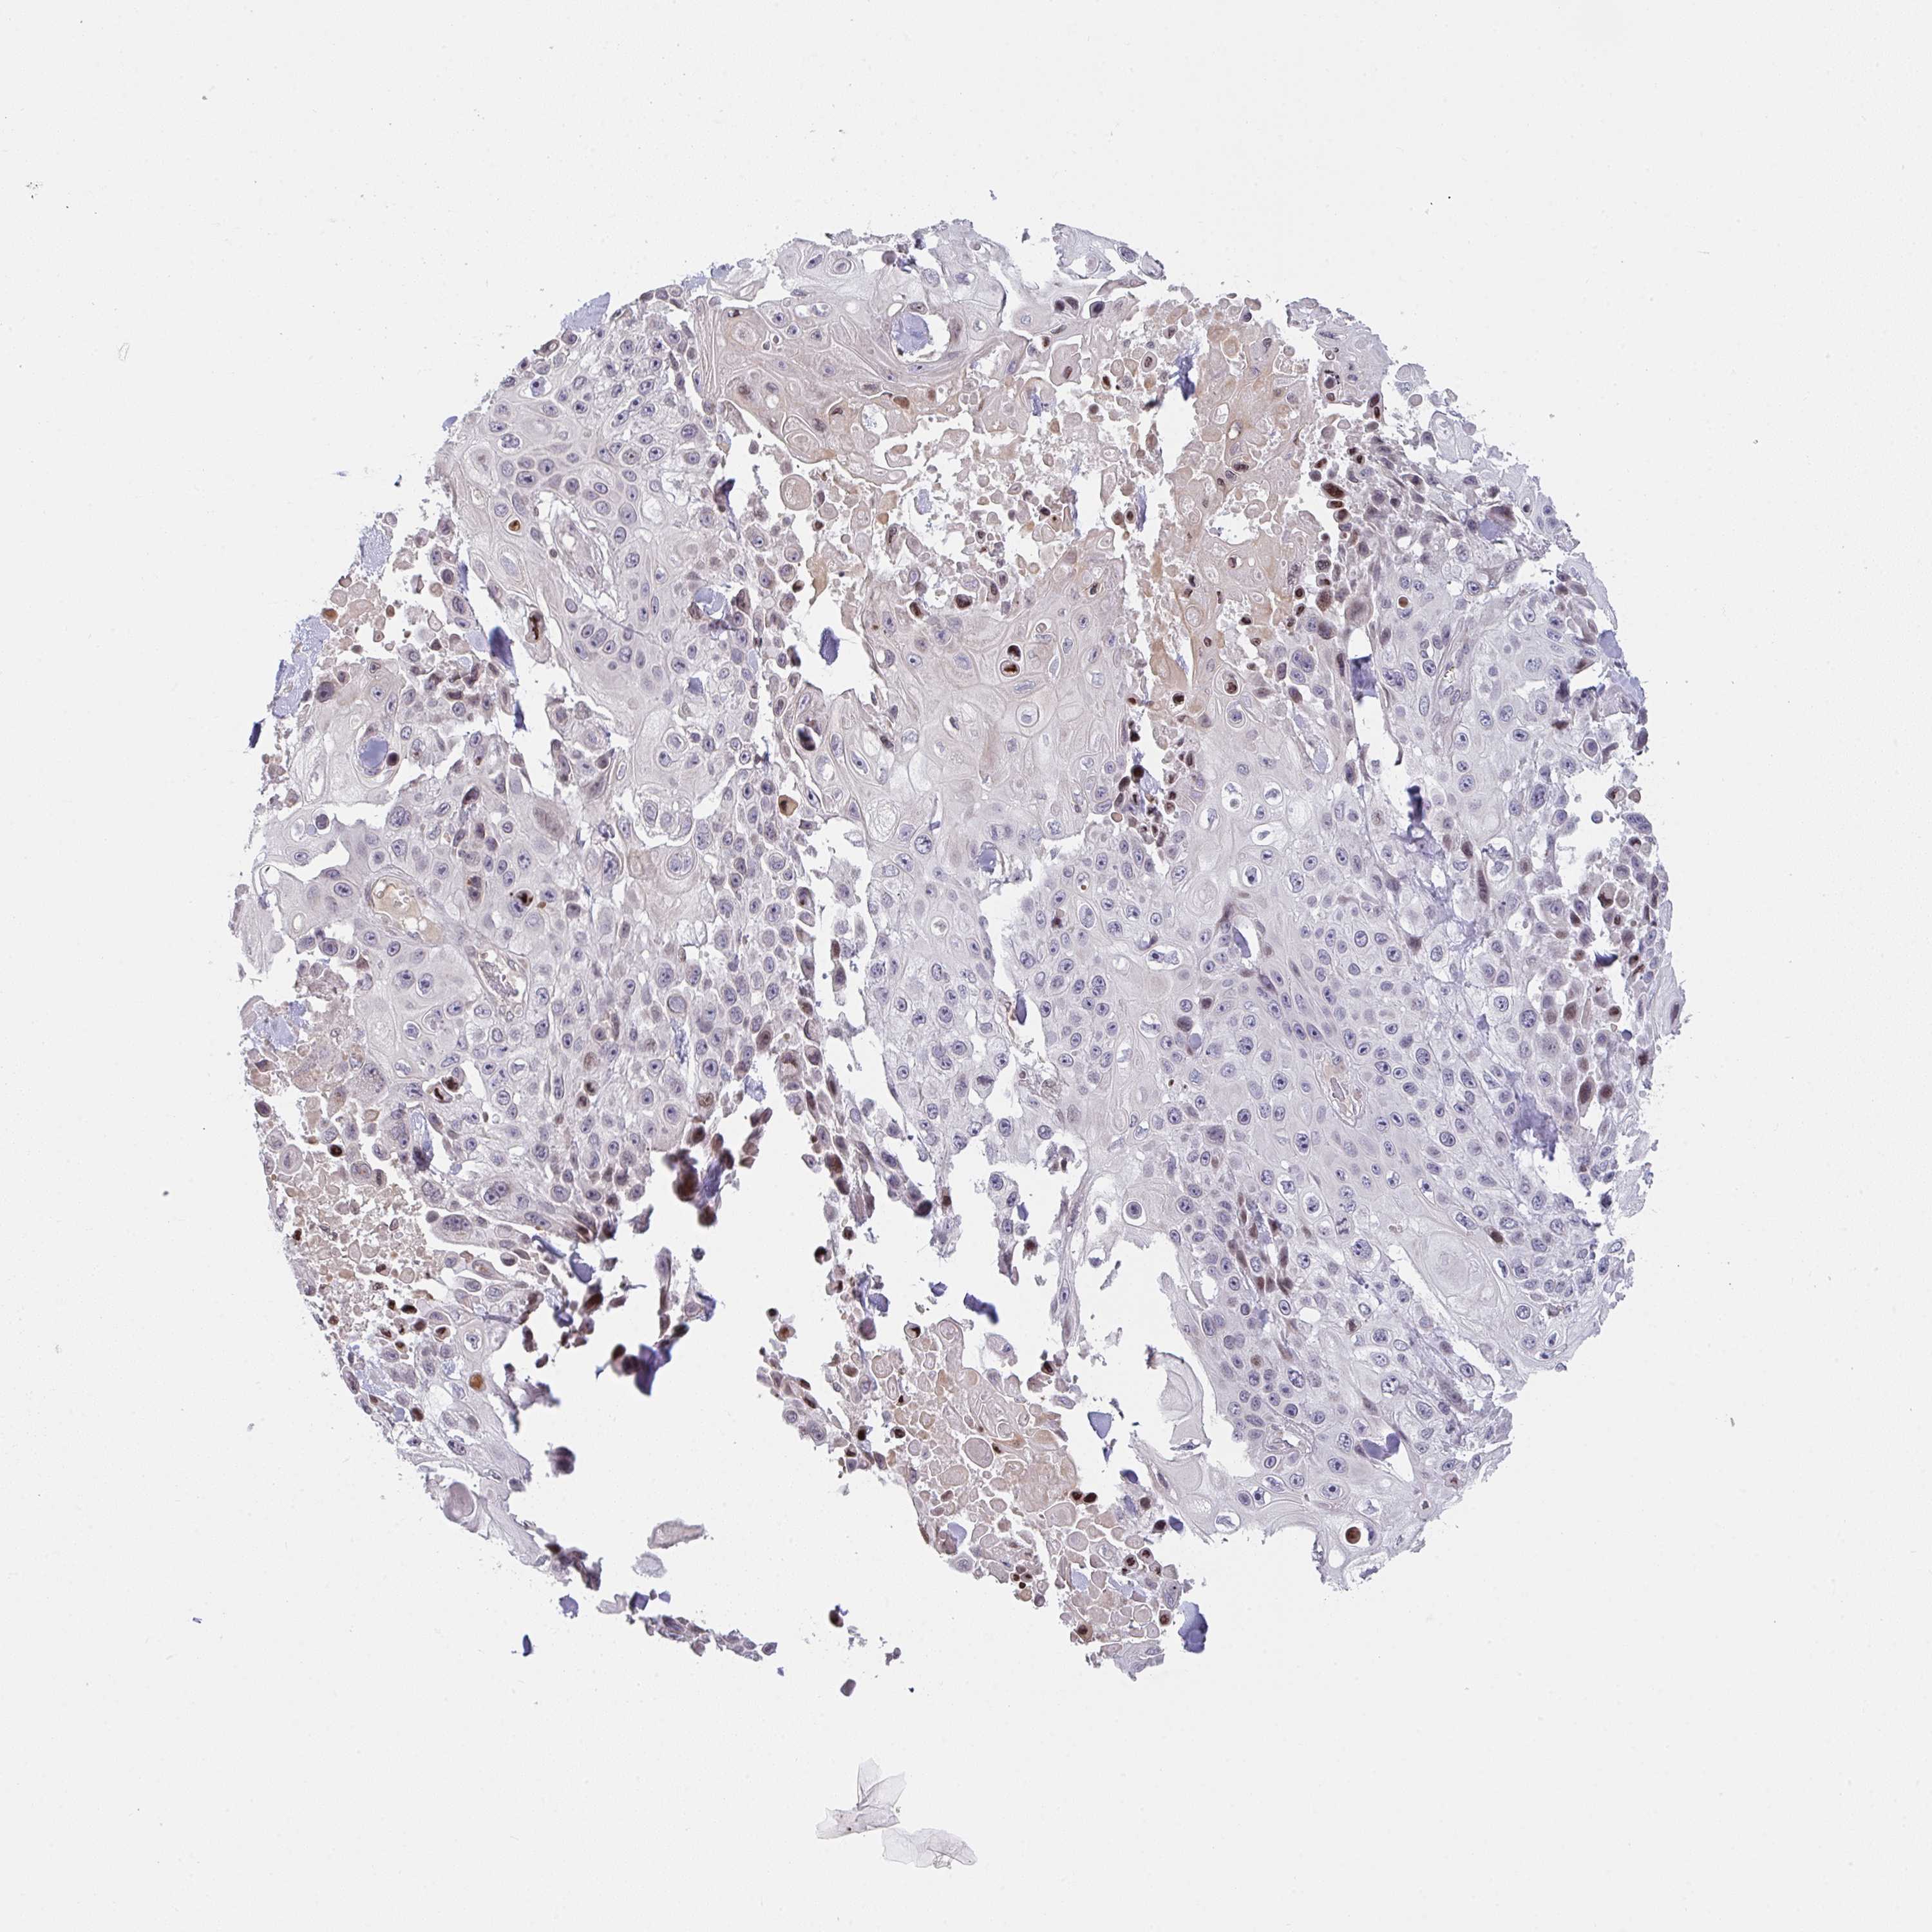

SKIN CANCER - Protein expressioni

A mouse-over function shows sample information and annotation data. Click on an image to view it in a full screen mode. Samples can be filtered based on level of antibody staining by selecting one or several of the following categories: high, medium, low and not detected. The assay and annotation is described here.

Antibody staining in the annotated cell types in the current human tissue is reported as not detected, low, medium, or high, based on conventional immunohistochemistry profiling in selected tissues. This score is based on the combination of the staining intensity and fraction of stained cells.

Each image is clickable and will lead to virtual microscopy that enables deeper exploration of all samples and also displays staining intensity scores, fraction scores and subcellular localization as well as patient and tissue information for each sample.

Antibody HPA057773

Squamous cell carcinoma, NOS